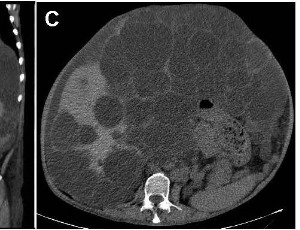

Polycystic liver in autosomal dominant polycystic kidney disease

A 61-year-old man presented for routine health checkup. The patient was asymptomatic. His medical history was autosomal dominant polycystic kidney disease (ADPKD). Laboratory results and urinalysis were unremarkable. Abdominal computed tomography showed innumerable hepatic cysts of different sizes and diffuse small renal cysts (Figures 1A-1C). Polycystic

J Clin Exp Gastroenterol, 2025, Volume Volume 4, Issue Issue 1, p15-16 | DOI: 10.46439/gastro.4.025